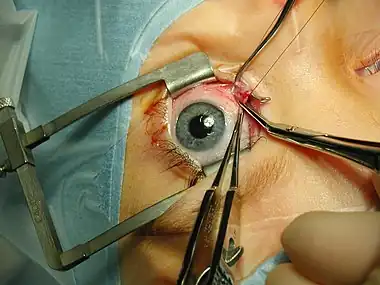

Medicine is the science and practice of caring for a patient, managing the diagnosis, prognosis, prevention, treatment, palliation of their injury or disease, and promoting their health. Medicine encompasses a variety of health care practices evolved to maintain and restore health by the prevention and treatment of illness. Contemporary medicine applies biomedical sciences, biomedical research, genetics, and medical technology to diagnose, treat, and prevent injury and disease, typically through pharmaceuticals or surgery, but also through therapies as diverse as psychotherapy, external splints and traction, medical devices, biologics, and ionizing radiation, amongst others.

Medicine has been practiced since prehistoric times, and for most of this time it was an art (an area of creativity and skill), frequently having connections to the religious and philosophical beliefs of local culture. For example, a medicine man would apply herbs and say prayers for healing, or an ancient philosopher and physician would apply bloodletting according to the theories of humorism. In recent centuries, since the advent of modern science, most medicine has become a combination of art and science (both basic and applied, under the umbrella of medical science). For example, while stitching technique for sutures is an art learned through practice, knowledge of what happens at the cellular and molecular level in the tissues being stitched arises through science.